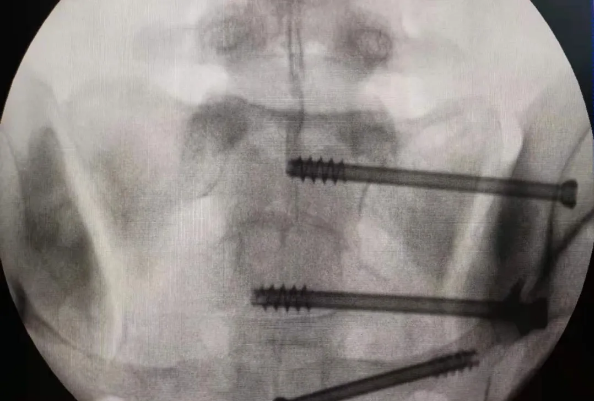

在南昌市第一医院廖琦教授向导下,,,,,由创伤骨科团队借助天玑?骨科手术机械人为患者“量身定做”最理想、最清静的教科书般的通道,,,,,完善清静微创完成手术,,,,,并且手术时间显着缩短,,,,,真正做到“指哪儿打哪儿”!更让患者定心的是,,,,,天玑?骨科手术机械人的“稳固手”机械臂举行精准定位,,,,,不必重复探寻。。。。。。

由于天玑?骨科手术机械人的精准及高效,,,,,可以使手术时间显着缩短,,,,,因此在骨盆骨折手术后,,,,,在廖琦教授指导下,,,,,脊柱外科团队使用天玑?骨科手术机械人同样为20岁女性腰椎骨折患者“量身定做”最理想、最清静的教科书般的通道,,,,,完善清静微创完成手术,,,,,手术不但时间缩短,,,,,并且出血和透视镌汰。。。。。。